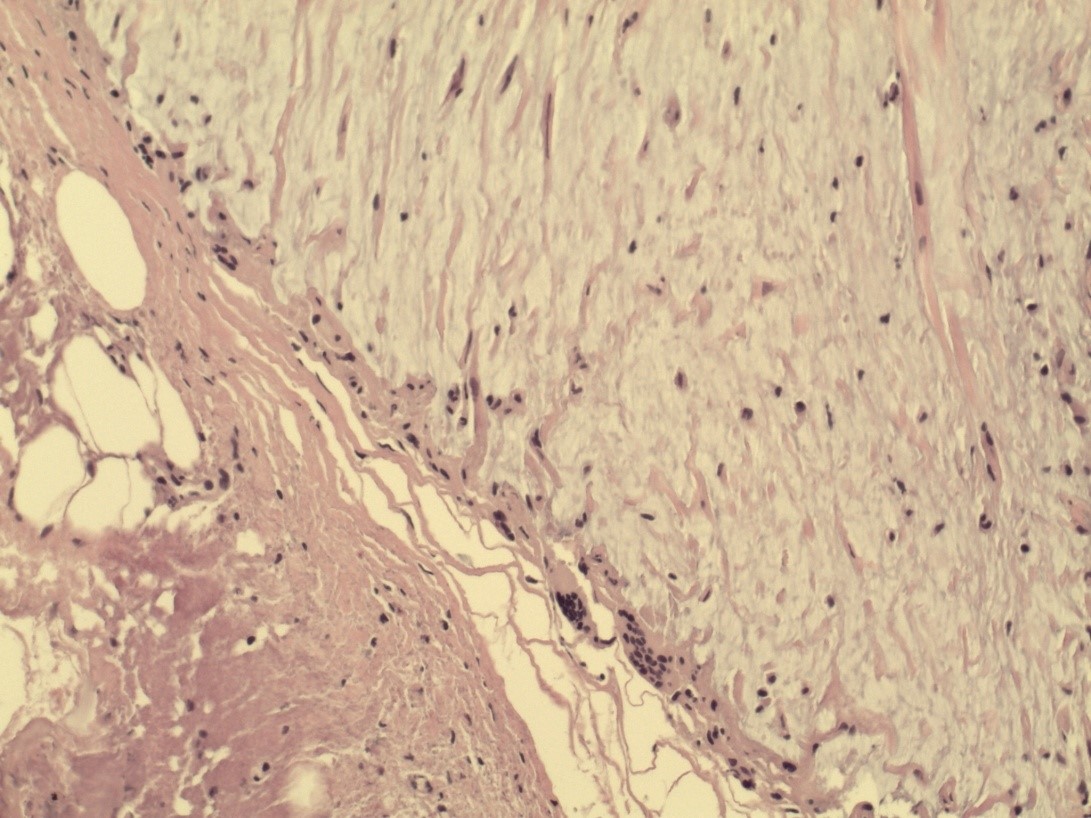

Гистологическая картина ПАМС до начала комплексного лечения была типичной и совпадала с описаниями других исследователей [22–26]. По всем полям визуализировали скопления гомогенных инородных тел (ПААГ), характер которых зависел от количества введенного геля, глубины и давности его залегания в мягких тканях, а также интенсивности его межтканевой миграции (рис. 1). Вокруг больших массивов безоболочечного имплантата, в основном сохранившего свою гомогенную базофильную структуру, прослеживалась тонкая соединительнотканная капсула толщина 50–120 мкм. Она состояла из нескольких слоев коллагеновых волокон и фибробластов (рис. 2). Толщина капсулы была неодинаковой на всем протяжении. На некоторых участках заметно выраженное ее истончение, разволокнение, дегенеративные изменения вплоть до полного перерыва (рис. 3). Последнее было особенно заметно у пациенток с длительным, свыше 10 лет, анамнезом «гелевой» болезни, а также при миграции ПААГ в соседние области.

Рис. 2. Биоптат ткани молочной железы: соединительнотканная капсула вокруг крупных очагов полиакриламидного геля. Окраска гематоксилином и эозином (×40).